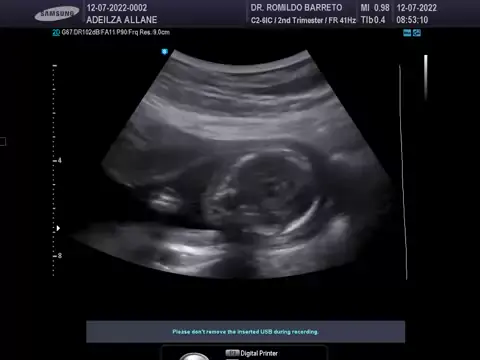

#maede3tres #bebêabordoAmor #Ultrassonografia #4mês